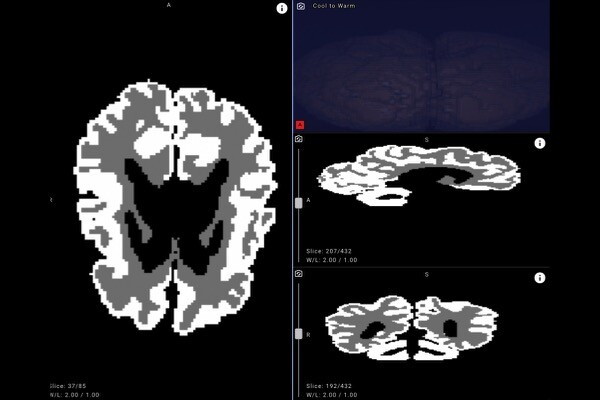

Система работает в облаке — специалист лучевой диагностики загружает результаты МРТ, причем данные анонимизируются. Нейросеть в течение нескольких минут выдает изображение с четко очерченными контурами и процентным соотношением белого и серого вещества.